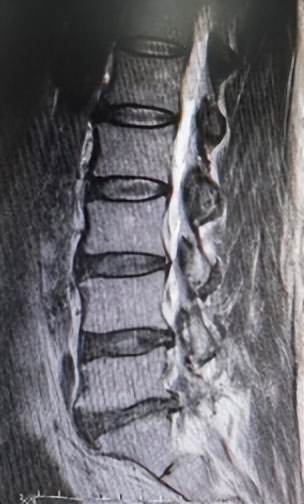

核磁显示腰4/5、腰5骶1椎管狭窄

61岁男性患者,腰4/5及腰5骶1两个节段椎管狭窄,腰痛伴左下肢放射性疼痛10年,伴有间歇性跛行,影响日常生活,保守治疗无效,但身体并发多种内科疾病,无法行开放手术,局麻下行微创椎间孔镜双节段减压。